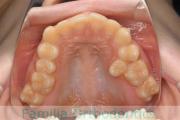

No.20V-496

- 叢生

- 年齢:

- 15歳

- 性別:

- 女性

- 抜歯部位

- 上:

- 84|58

- 下:

- 8558

全体的なでこぼこを治したいということで来院されました。上顎は右は4,左と下顎両側は5番を抜歯して、マルチブラケット法にて治療を行いました。2年強、25回程度の通院をしていただきました。

非常に強いでこぼこですので、後戻りのリスクは高めであると思われます。

- ≫治療前

-

上顎